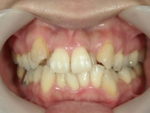

空隙歯列(くうげきしれつ)

顎の大きさにくらべ、歯が小さかったり本数が少なかったために、隙間ができてしまう歯並びをいいます。前歯の間に隙間がある場合は正中離開(せいちゅうりかい)、全体に隙間がある場合は空隙歯列といいます。一般的には、すきっ歯と呼ばれています。